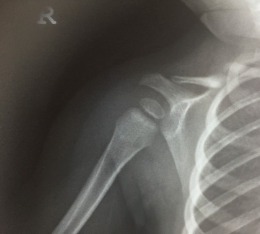

Right congenital clavicle pseudoarthrosis

A six year old girl who presented with right clavicle congenital pseudoarthrosis. Excellent functional outcome following surgical intervention.